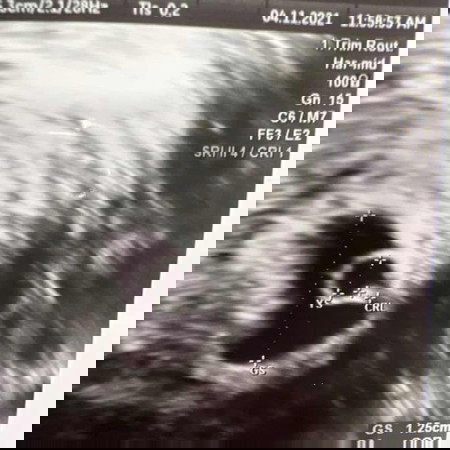

ไปอัลตร้าซาวน์มาค่ะ คุณหมอบอกว่าประมาณ 5 วีค ถือว่าเล็กไปไหมคะ นัดอีกทีอาทิตย์หน้าค่ะ ตอนนี้ค่อยข้างกลุ้มใจมาก เพราะเห็นถุงตั้งครรภ์ เห็นถุงไข่แดง เห็นตัวเบบี๋ แต่ยังไม่สามารถฟังเสียงหัวใจได้ค่ะ อยากขอความคิดเห็นจากแม่ๆทุกคน ท้องแรกกังวลไปหมดเลยค่ะ 😔😔